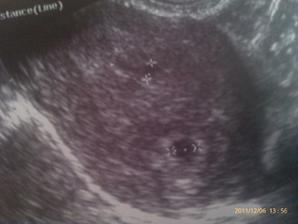

Ultrazvuk dvojiciek?